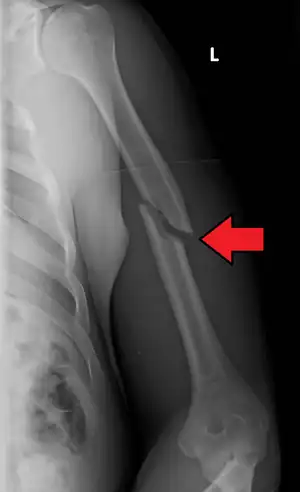

Fratura de úmero

Fratura de úmero se refere a ruptura do úmero, o maior osso do braço. As fraturas proximais são próximas ao ombro (25% dos casos), mediais na diáfise (60% dos casos) e as distais ocorrem próximo ao cotovelo (15% dos casos). Essa classificação pode ser subdividida, com base na extensão da fratura e nas partes específicas do úmero. [1]

Quando há suspeita clínica são solicitadas duas radiografias, frente e perfil ou duas oblíquas, dependendo do local afetado. Tomografia computadorizada pode dar mais informações sobre a fratura.[8]